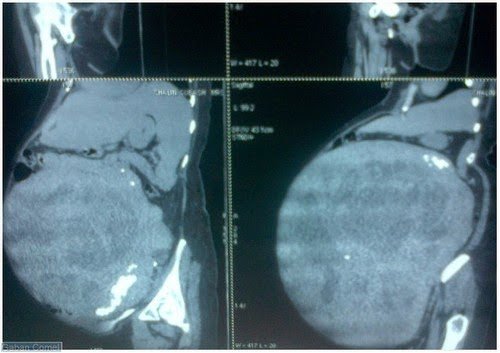

Sepasukan doktor di sini berjaya melakukan pembedahan rumit ke atas seorang wanita untuk mengeluarkan ketumbuhan dalam rahim seberat 14 kilogram dan berukuran lilit 53 sentimeter, yang terbesar dalam dunia.

Doktor yang menjalankan ujian mendapati dia terlalu lesu sebelum mengesan ketumbuhan besar pada permukaan luar rahim yang menyebabkan tekanan pada tubuhnya.

Menurutnya, fibroid terbesar pernah dikeluarkan pakar perubatan sebelum ini ialah di Afrika yang seberat 10 kilogram.

Pakar bedah, Dr Shiva Kumar berkata, pasukan empat doktor mengambil masa tiga jam setengah untuk membuang fibroid berkenaan.